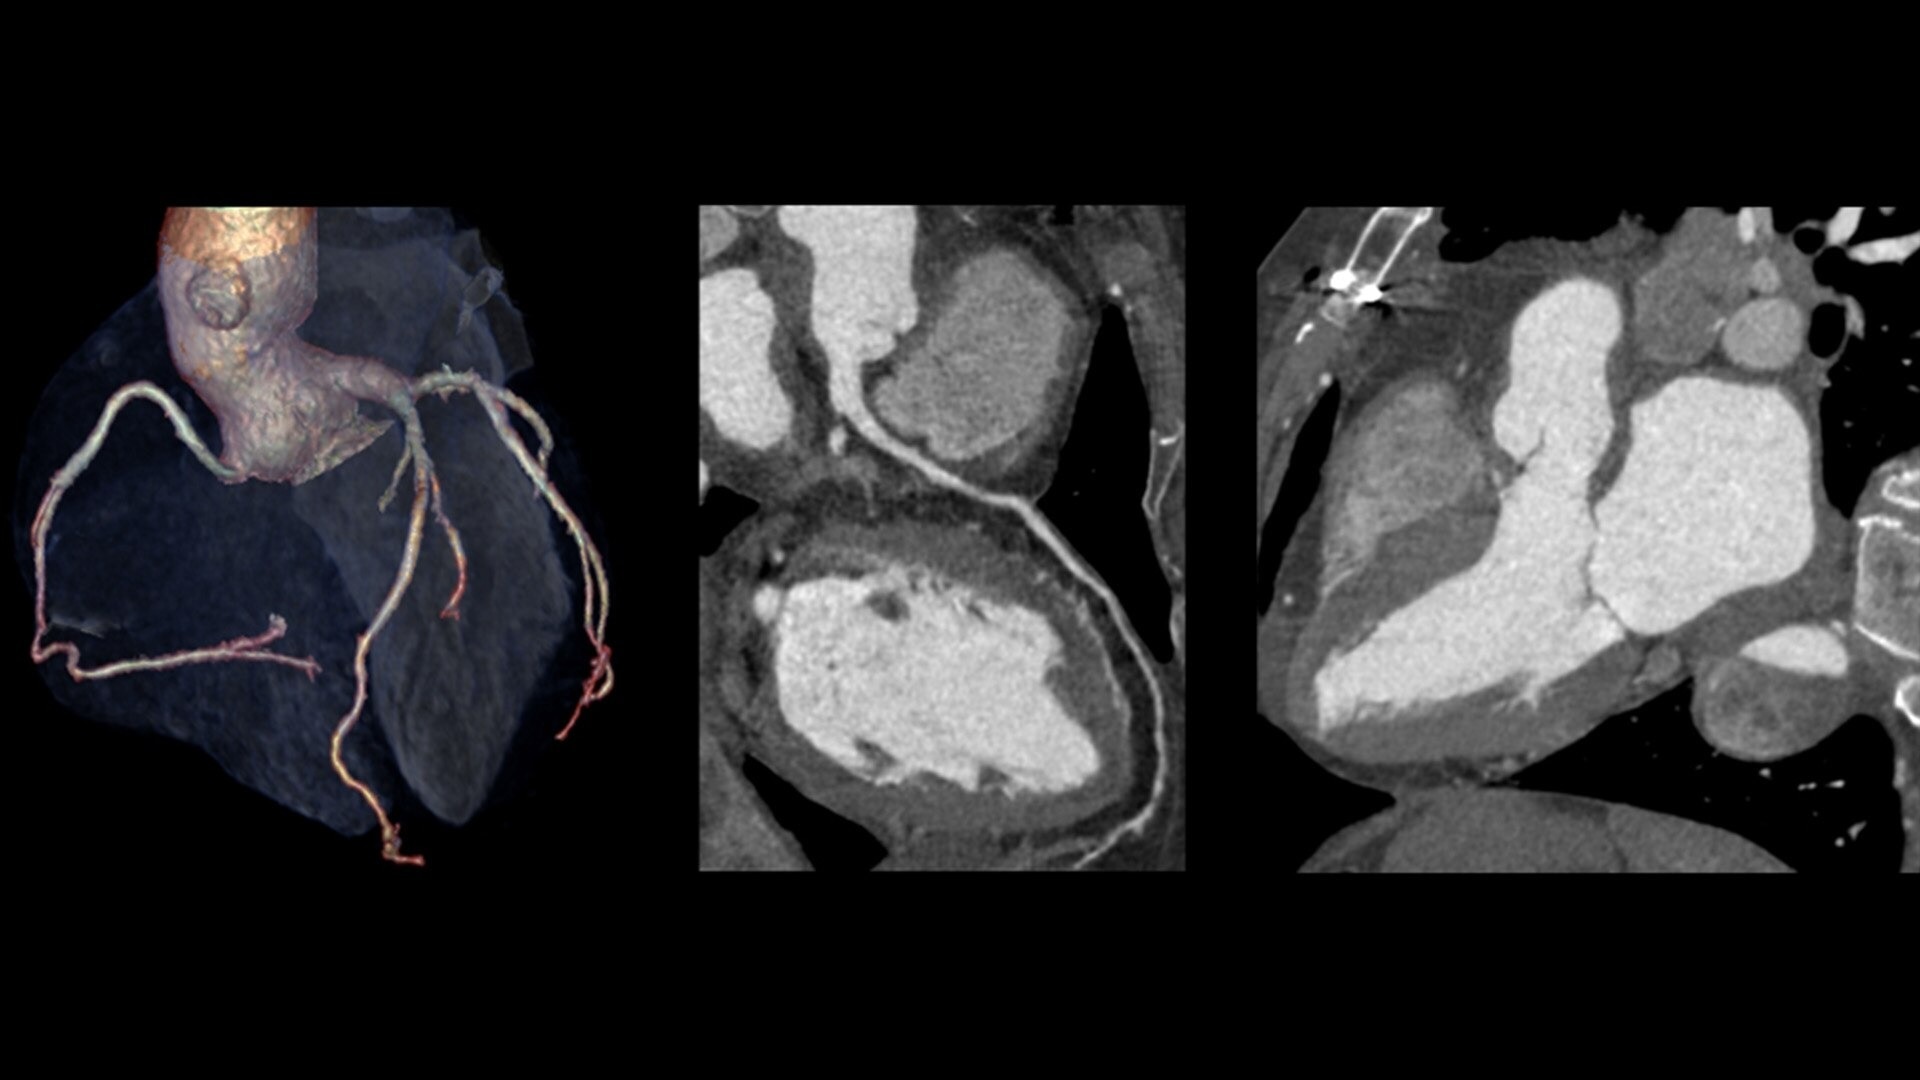

The ECG-less CT (a cardiac CT scan without an ECG trace) is an industry-first

Increases Cardiac CT access

Address cardiac exams where patient access and speed need to be prioritized